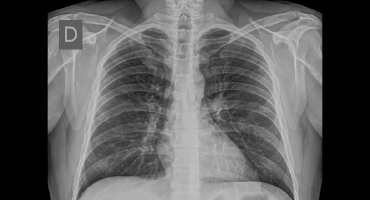

NEUMOTORAX ESPONTANEO

Rayos X